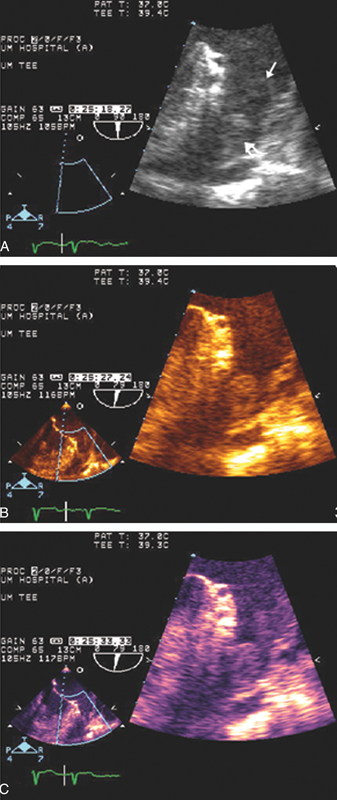

فحوصات تشخيصية لبعض امراض القلب والشرايين التاجية